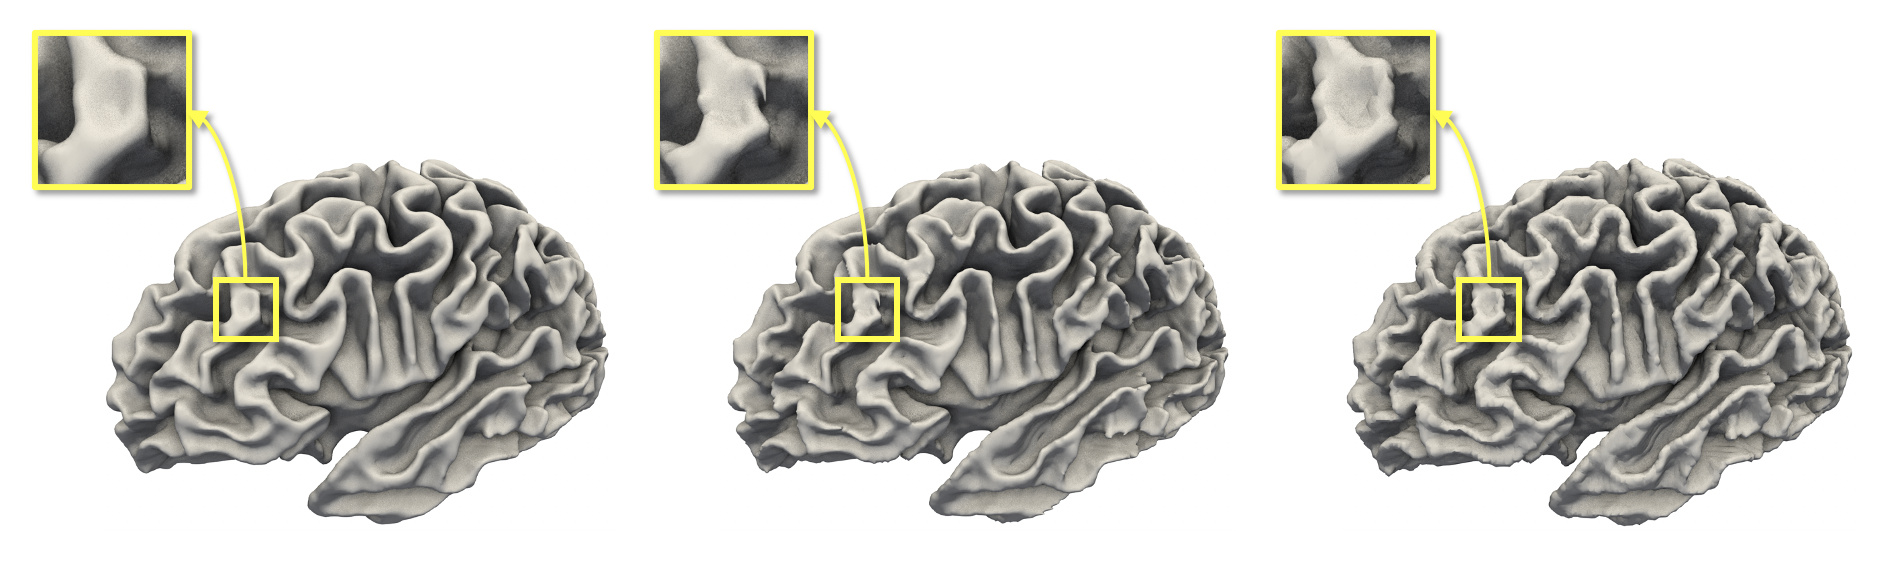

Refer to caption

Figure 1: A diffeomorphic flow modeled by CortexODE. A WM surface (leftmost) is deformed into a pial surface (rightmost).